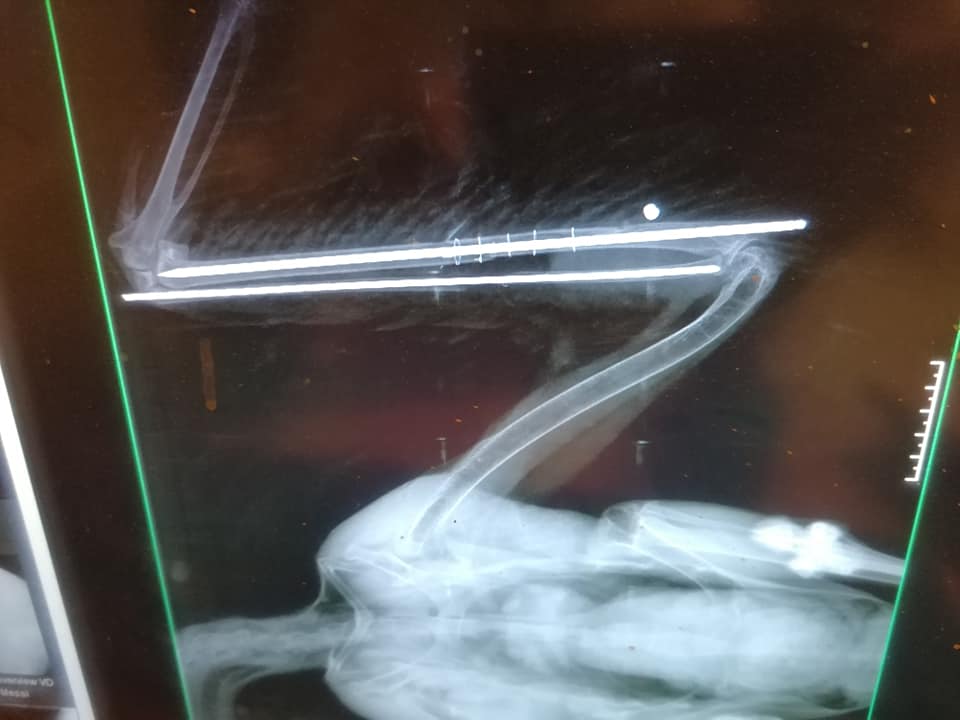

Mint írják, szerdán majdnem egyszerre szállítottak be egy légpuskával meglőtt fehér gólyát (fokozottan védett faj, eszmei értéke 100 ezer forint) és egy szabálytalanul kihelyezett csapóvas által fogott barna rétihéját (védett, eszmei értéke 50 ezer forint). Előbbi valószínűleg fészkel, tojásai jelenleg árván maradtak. A lövedék a madár felkarcsontját roncsolta, gyógyulása több mint 2 hónapig is eltarthat. Utóbbinak a csapóvas majdnem letörte a lábfejét, az állat jelenleg is válságos állapotban van.